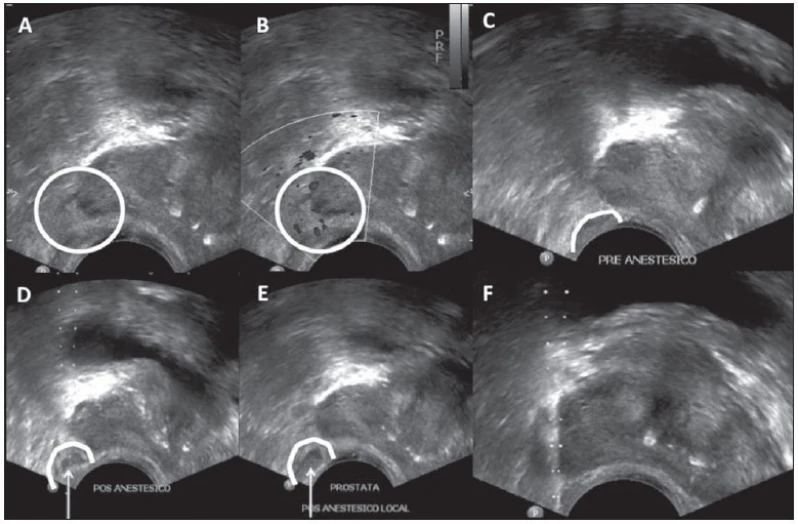

A vasectomia é um procedimento cirúrgico que consiste na ligação ou corte dos canais deferentes, impedindo a passagem dos espermatozoides e, consequentemente, a fertilização. É uma opção contraceptiva permanente e segura para homens que não desejam ter filhos ou que já possuem o número desejado. A cirurgia é realizada com anestesia local e dura cerca de 30 minutos. Após o procedimento, é necessário um período de repouso e uso de analgésicos. A eficácia da vasectomia é de cerca de 99%, mas é importante lembrar que não protege contra doenças sexualmente transmissíveis. É recomendado que o paciente faça um acompanhamento com um urologista após a cirurgia. Na DK Urologistas, contamos com uma equipe especializada em vasectomia e oferecemos todo o suporte necessário para os nossos pacientes.